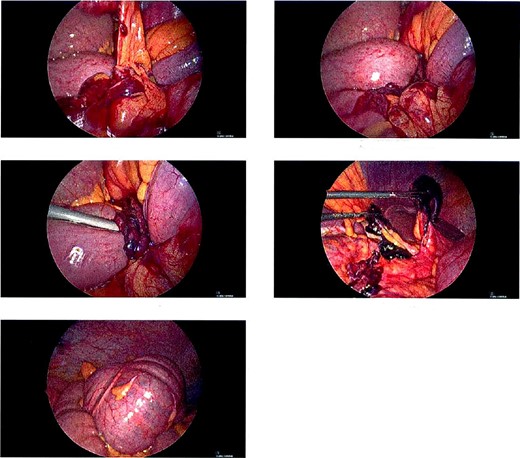

A 68-year-old male with a history of hypertension and no past surgical intervention presented with 2 days of diffuse abdominal pain, anorexia, and nausea. On admission, his vitals included a temperature of 98.2°F, BP of 149/79, pulse of 64, and SpO2 of 97% with a mildly distended abdomen with tenderness in the umbilical and epigastric regions. The labs were unremarkable. CTA/P showed two separate areas of mesenteric swirling: one contiguous to the distal small bowel, resulting in small bowel obstruction, and another at the distal transverse colon (Fig. 1A–C). The cecum was noted to be in the right upper quadrant. The patient was emergently taken to the OR and underwent a diagnostic laparoscopy. A cecal bascule was noted in addition to an internal hernia caused by a thick adhesive necrotic band arising from the colonic mesentery and omentum (Fig. 2). The bowel was viable, and the band was resected. The transverse colon was tortuous, but no hernia was seen. The cecum was brought down to the right lower quadrant, and a cecopexy to the abdominal wall was performed. The patient had an unremarkable postoperative course and was discharged on postoperativhernia was seen. The cecum was brought down to the right lower quadrant, and a cecopexy to the abdominal wall was performed. The patient had an unremarkable postoperative course and was discharged on postoperative Day 2.

Intraoperative pictures of thick necrotic/adhesive band arising from colon mesentery entrapping band. Cecal bascule found in the RUQ.